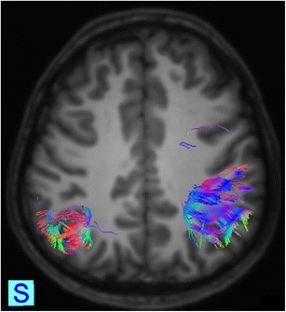

Fig. 3